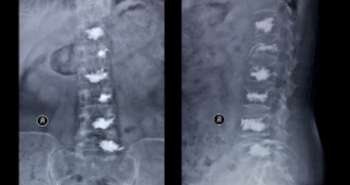

Currently, available osteoarthritis treatment approaches intend to reduce the pain and control joint function. The only pain relief medications used to relieve osteoarthritis-related pain are the non-prescription oral non-steroidal anti-inflammatory drugs.This post-hoc pooled study intended to assess the analgesic effectiveness and safety of two non-prescription doses of Naproxen sodium for short-term use among the subjects with hip or knee osteoarthritis. A different sub-group analysis was performed with the elder individuals who obtained a lower dose of Naproxen sodium.

The oral Naproxen sodium or placebo was given above seven days as per the four multi-centre, randomised, parallel, multi-dose, double-blind, placebo-controlled studies. A total of 818 subjects who obtained Naproxen sodium or placebo were pooled and examined at baseline and after seven days. Timed 50-foot walk test used to measure the function and Five-point rating scales to stiffness after rest, patient and investigator assessment of treatment, day and night pain, and knee or hip joint pain.